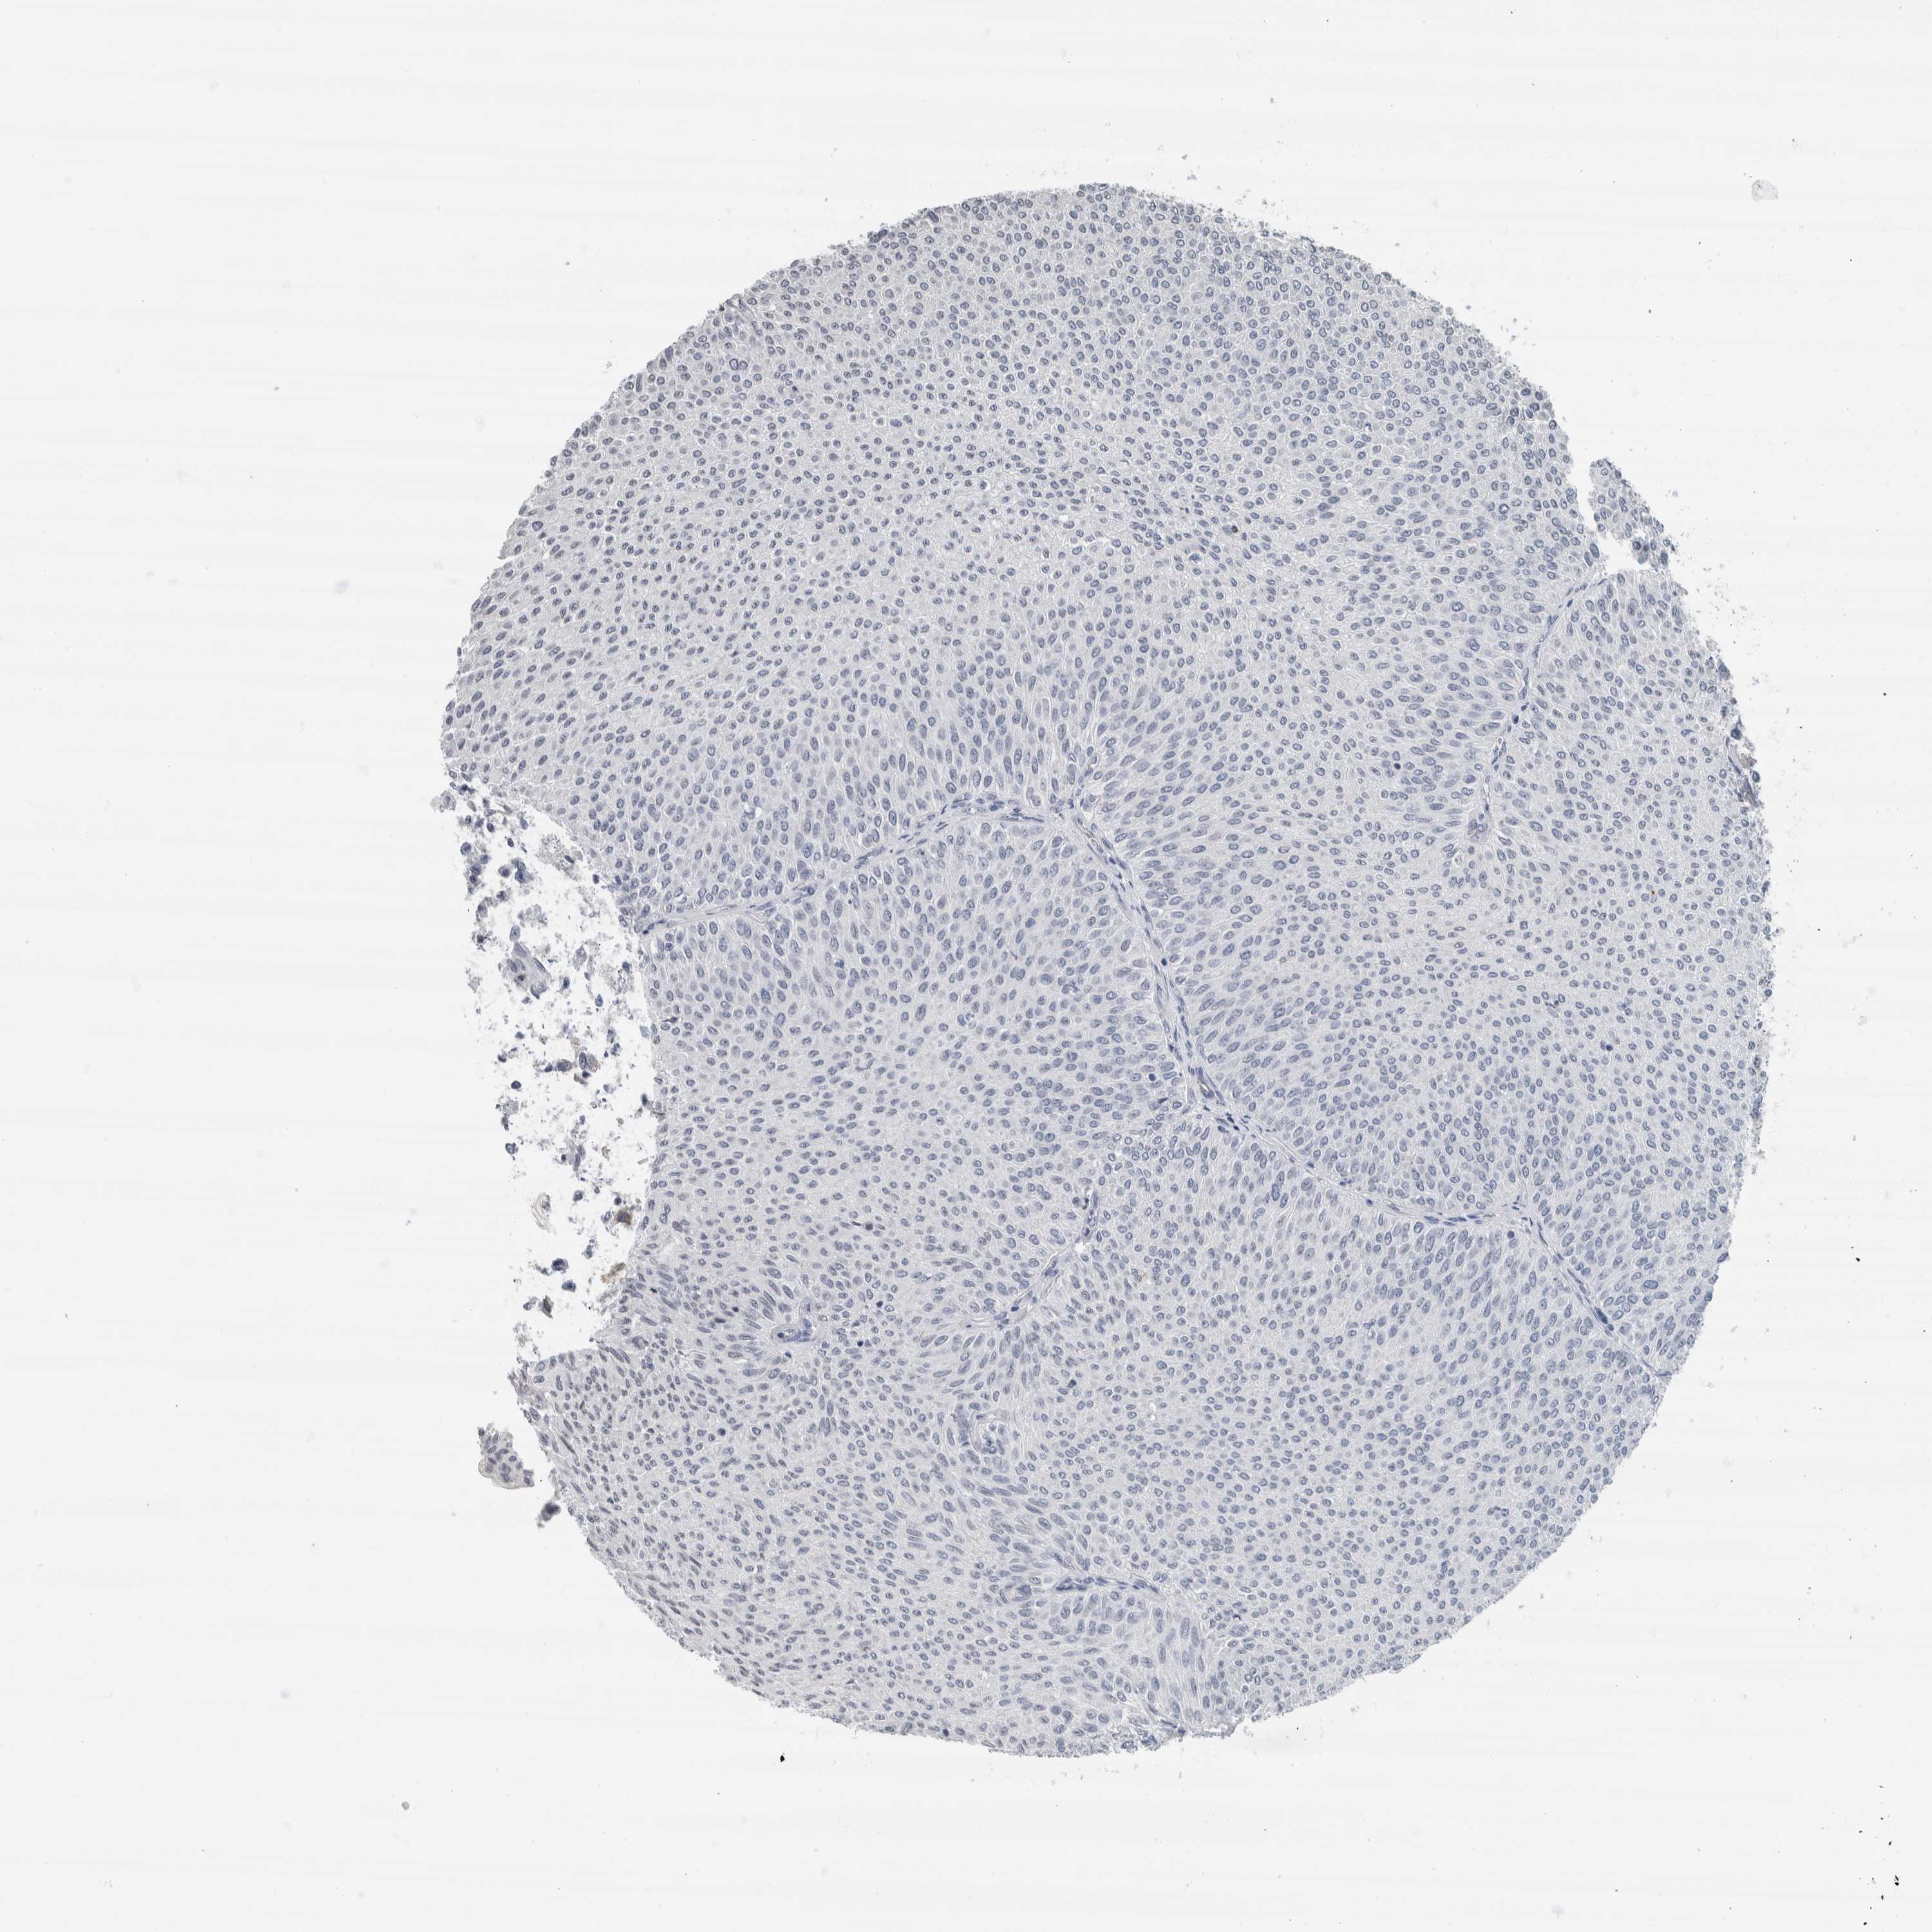

UROTHELIAL CANCER - Protein expressioni

A mouse-over function shows sample information and annotation data. Click on an image to view it in a full screen mode. Samples can be filtered based on level of antibody staining by selecting one or several of the following categories: high, medium, low and not detected. The assay and annotation is described here.

Note that samples used for immunohistochemistry by the Human Protein Atlas do not correspond to samples in the TCGA dataset.

Antibody stainingi

Antibody staining in the annotated cell types in the current human tissue is reported as not detected, low, medium, or high, based on conventional immunohistochemistry profiling in selected tissues. This score is based on the combination of the staining intensity and fraction of stained cells.

Each image is clickable and will lead to virtual microscopy that enables deeper exploration of all samples and also displays staining intensity scores, fraction scores and subcellular localization as well as patient and tissue information for each sample.

Antibody HPA022845

Antibody HPA023138

Antibody CAB010900

Antibody CAB012976

Staining

High

Medium

Low

Not detected

Intensity

Strong

Moderate

Weak

Negative

Quantity

>75%

75%-25%

<25%

None

Location

Nuclear

Cytoplasmic/membranous

Cytoplasmic/membranous,nuclear

Urothelial carcinoma, Low grade

Urothelial carcinoma, High grade